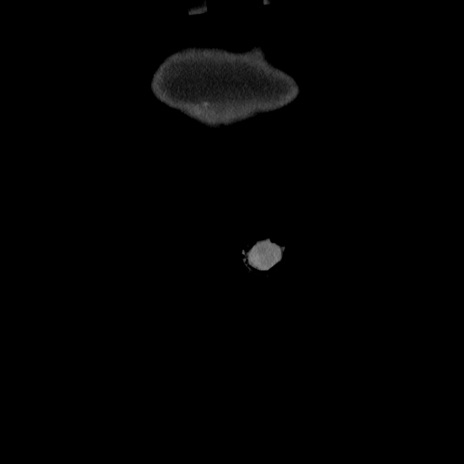

矢状断像